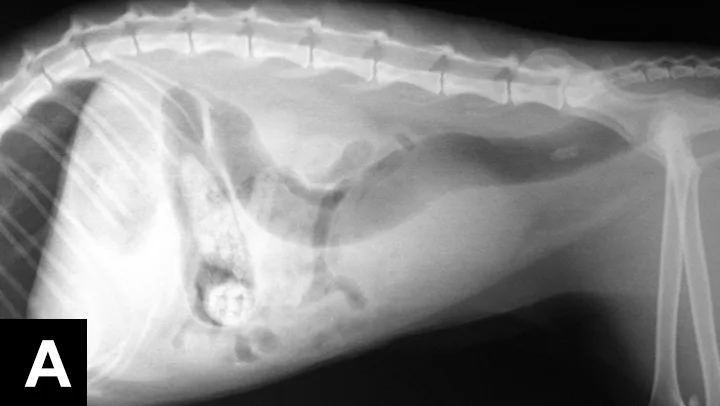

Tests for FIV and FeLV were negative. CBC revealed a mild monocytosis and neutrophilia. A serum chemistry panel revealed azotemia and mild hyperglycemia (Table 1). Urinalysis via cystocentesis revealed concentrated urine with RBCs too numerous to count and mucus strands. The remainder of the urinalysis was within normal limits. No bacteria were seen. Urine culture was negative. Survey radiographs revealed a gas pattern in the GI tract, an enlarged bladder, and ileus throughout the small bowel (Figure 1). No stones were visible in the kidneys, ureters, bladder, or urethra.

Figure 1

Lateral (A) and ventrodorsal (B) radiographs showed a distended urinary bladder, ileus, and a GI obstructive pattern with possible gastric and small bowel foreign bodies.